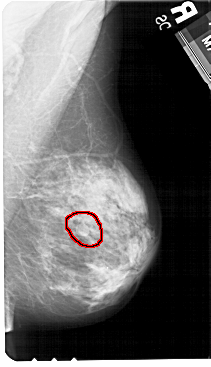

FILE: A_1322_1.RIGHT_CC.OVERLAY

TOTAL_ABNORMALITIES 1

ABNORMALITY 1

LESION_TYPE MASS SHAPE ROUND MARGINS OBSCURED

ASSESSMENT 4

SUBTLETY 2

PATHOLOGY BENIGN

TOTAL_OUTLINES 1

BOUNDARY